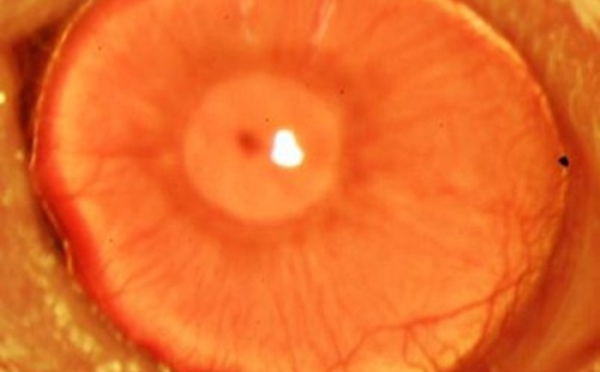

Primera regeneración de córnea con células madre humanas de adulto - 03/07/2014

El limbo esclerocorneal es una parte de la córnea del ojo esencial para la visión. Si presenta insuficiencia, el paciente puede perder la vista. Ahora, científicos estadounidenses han encontrado una manera de regenerar el tejido de esa parte de la córnea, usando células madre humanas y una molécula “guía”. En un futuro, el proceso podría curar algunos tipos de ceguera.